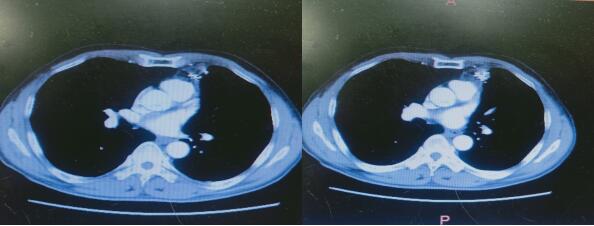

↑ 粒子植入

粒子植入是将放射性离子以预定的排列方式,通过影像引导下体外穿刺的手段放置进肿瘤内,通过粒子放射出来的短程射线对肿瘤产生杀伤,其射线范围小,对周围正常组织影响小,对医务人员和患者周围人员无损伤,对环境无影响,是目前治疗中晚期肿瘤的有效方法。